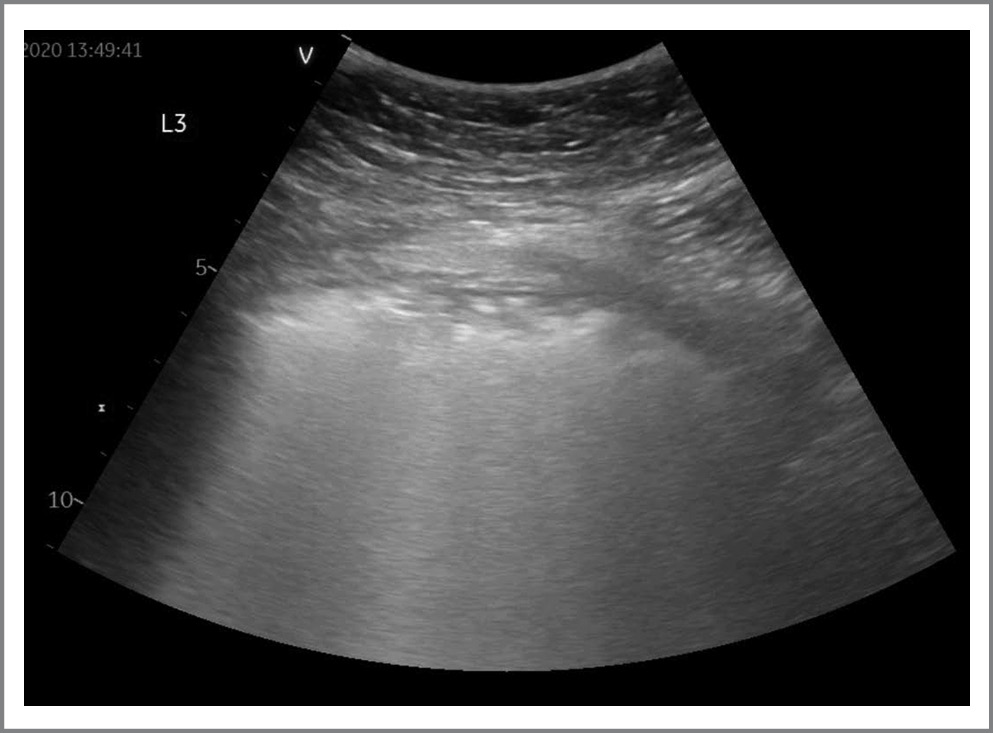

По данным УЗ-протокола у подавляющего большинства (n=33; 91,6%) пациентов прослеживались В-линии. У 26/36 (72,2%) пациентов выявлены патологические изменения в легких в виде участков консолидации (рис. 2). У 6/36 (16,6%) пациентов по данным УЗИ определялись изменения по типу «белое легкое», что соответствовало картине КТ-3–4 (рис. 3). Согласно данным литературы считается, что наличие консолидаций соответствует более тяжелому поражению легких по сравнению с множественными В-линиями [2, 8]. Однако мы, основываясь на собственном опыте, с учетом клинической картины, КТ-диаг- ностики и лабораторных данных отнесли изменения по типу сливных В-линий – «белого легкого» – к наиболее тяжелым поражениям у пациентов с COVID-19. Также к наиболее тяжелому поражению легких можно отнести сочетание отсутствия аэрации («белое легкое») с транслобарными консолидациями и аэробронхограммами.

Рис. 2. УЗИ легких у пациента с COVID-19. На рис. представлены субплевральные консолидации. / Fig. 2. Lung ultrasound in a patient with COVID-19. The figure shows subpleural consolidations.